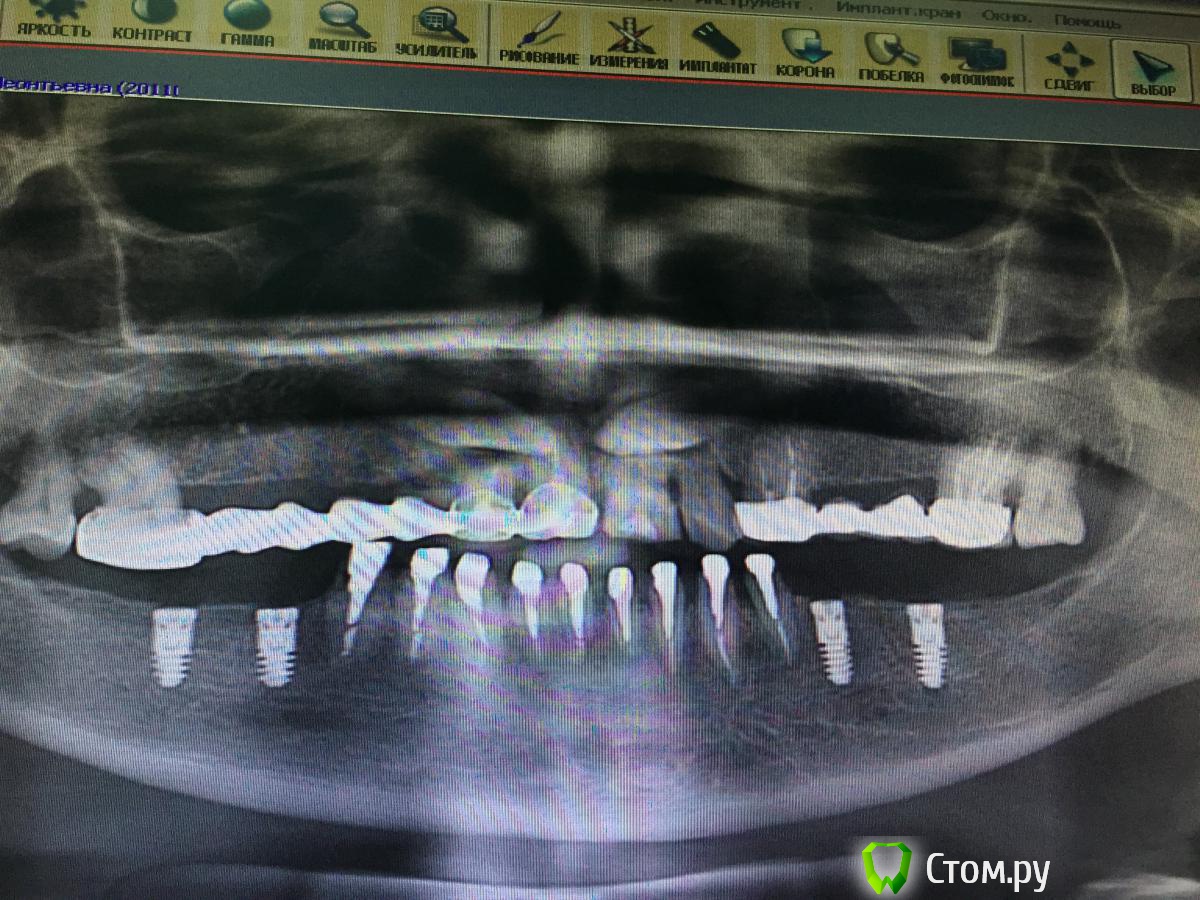

Opimar Опубликовано 18 ноября, 2014 Поделиться Опубликовано 18 ноября, 2014 Здравствуйте. Вот как мне кажется интересный случай. Пациентка 57 лет. На верхней челюсти одиночные 21,22. Мост на 11 и 12. Жалобы на подвижность и боли в области 11,12. На ОПТГ обнаружена ретенция, дистопия 13,23. Была направлена к терапевту для перелечивания 11,12,21 и 22. В процессе работы у терапевта возникли сомнения по поводу состоятельности корней зубов. Направлена на КТ. На КТ резорбция корней на 1/2 из-за клыков. Принято решение об удалении 11,12,21,22, ретенированных 13 и 23 с последующей костной пластикой и имплантацией через 6мес. Собственно сегодня выполнен первый этап: 1. Удалил 11,12,21,22 2. Трапецивидный лоскут от 11-22. 3. С помощью бор машины выпиливание 23 с разделением зуба на 2 фрагмента. 4.кюретаж лунки5.мобилизация лоскута6.заполнение лунки 23 Osteobiol mp3, сверху мембрана Evolution 7.фиксация лоскута Vicryl 4-0, Корален 4-0.Холод на область операции, антибиотикопрофилактику начали еще вчера.Удаление уложилось в 1.5 часа+ 30 мин подсадка и швы. Теперь вот думаю когда заниматься 13 и стоит ли? Может попытаться имплантанты мимо него поставить? Спасибо. Ссылка на комментарий

Opimar Опубликовано 18 ноября, 2014 Автор Поделиться Опубликовано 18 ноября, 2014 Оптг Ссылка на комментарий